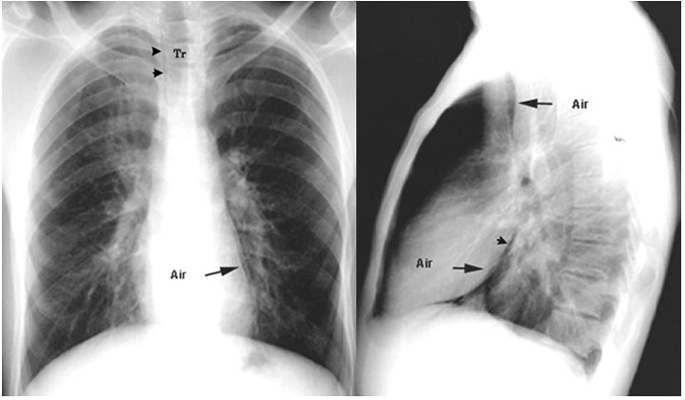

Asthmatic with Pneumomediastinum

Arrows point to air around heart and great vessels.